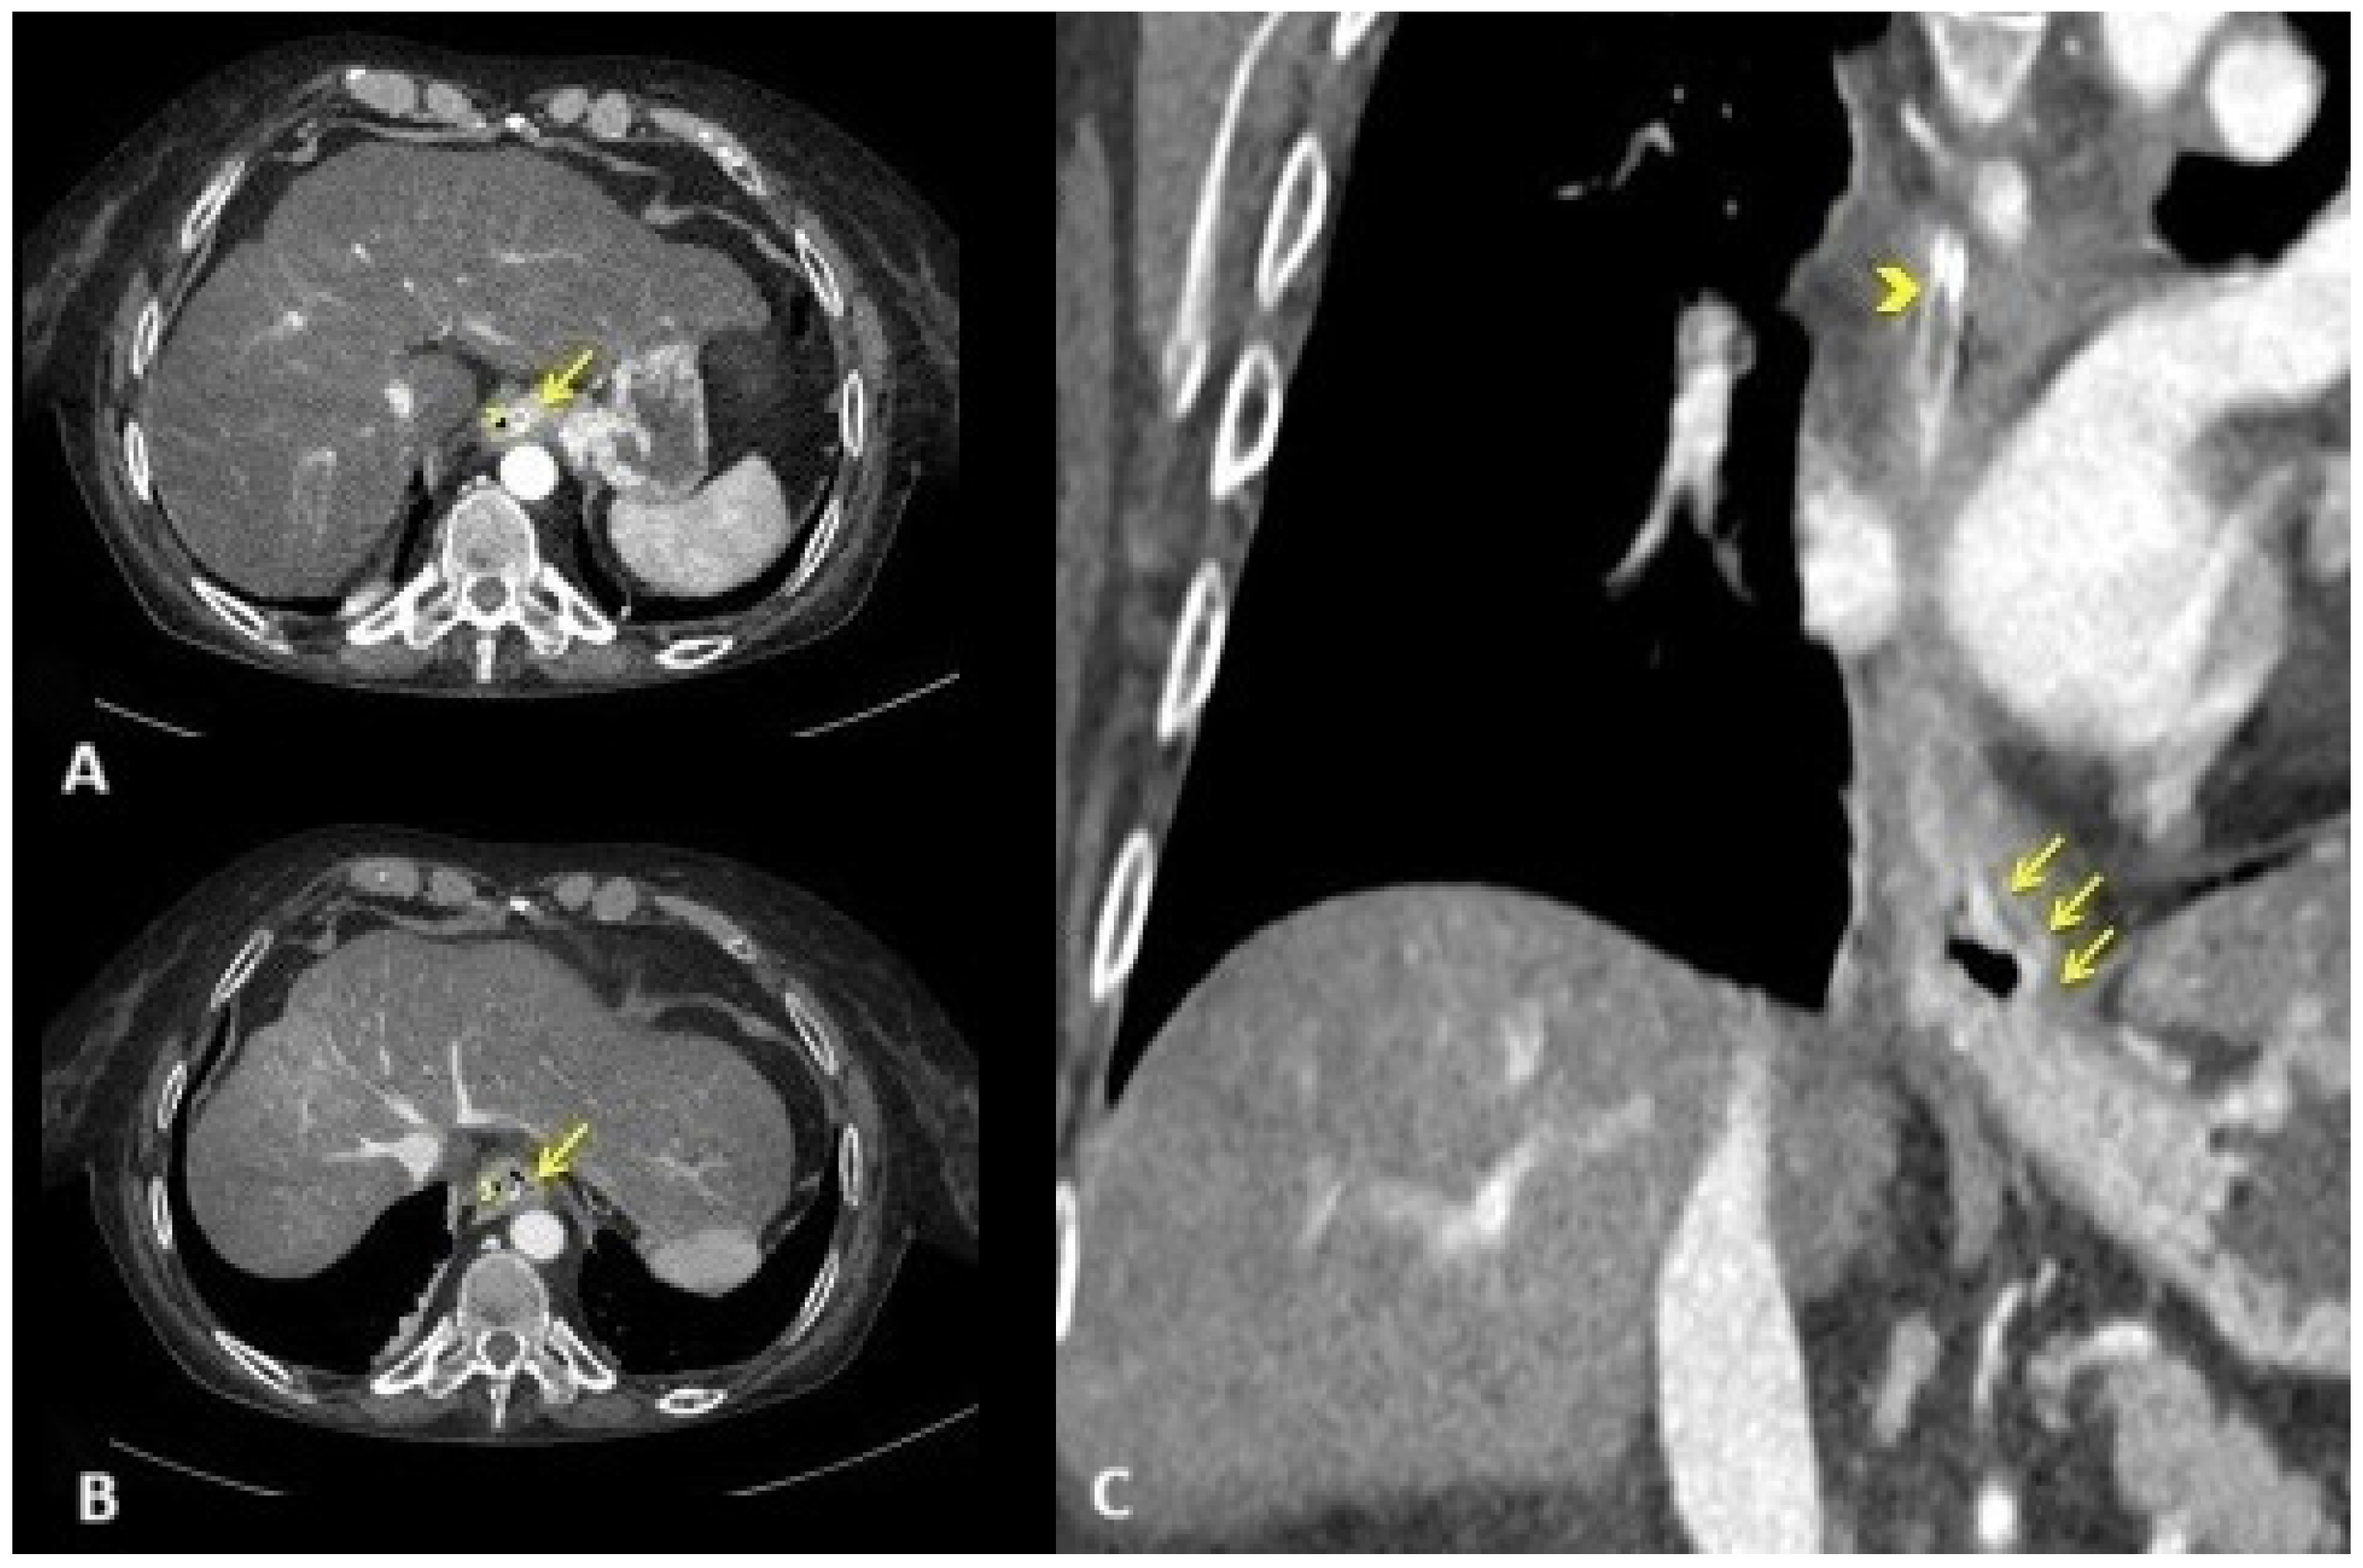

Fluids with 80 mL of 7% sodium bicarbonate, thiamine, and high-dose pantoprazole were administered intravenously. Then, an emergent computed tomography angiography was performed, demonstrating a grossly dilated gastric cavity alongside a thickened distal esophagus with evidence of transmural inflammation, in the absence of free air or active bleeding (Figure 1).

Figure 1.

Emergent computed tomography angiography. Axial arterial (A) CT scan at the level of the gastro-esophageal junction and venous (B) CT scan at the level of lower thoracic esophagus showing circumferential thickening of the esophageal wall. Note the mucosal enhancement ((A); yellow arrow) with wall hypoattenuation, producing the target sign ((B); yellow arrow). Coronal venous CT reconstruction showing extension of esophagitis predominantly to the distal third of the esophagus, including the gastro-esophageal junction ((C); yellow arrows). Nasogastric tube ((A–C); yellow arrowhead).